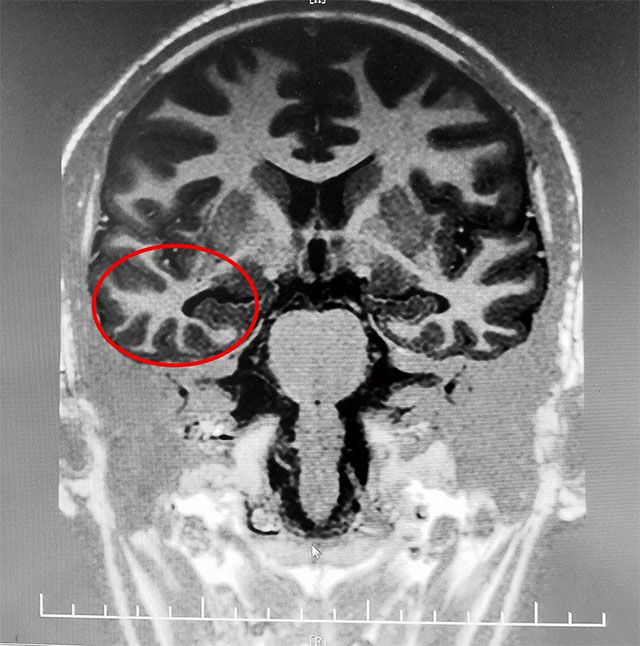

经检查,患者临床主要表现为复杂部分性发作继发全面性发作。脑电监测期间发作两次,24H长程视频脑电监测有明显异常波。MRS海马示:代谢异常,海马硬化。

综合各项检查最终明确治癫灶位于右侧额叶、右侧颞叶、右侧海马。患者经长期系统内科药物治疗不佳,确诊为难治性癫痫,并且经过系列检查可明确病变位置。经过系统全面评估,手术指征明确,未见明显手术禁忌。